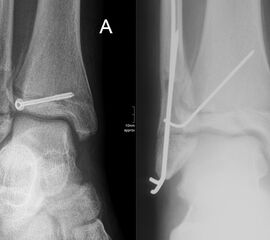

Ist die korrekte Stellung nur gegen einen federnden Widerstand zu erreichen, kann die Fraktur durch perkutane K-Drähte stabilisiert werden. Bei einer Fugenschaftfraktur mit großem Keil ist auch eine Schraubenosteosynthese möglich (Abbildungen 13 bis 14).

Behandlungsziel ist die exakte Rekonstruktion der Gelenkfläche sowie die Minimierung des Risikos einer späteren Wachstumsstörung. Dislozierte Frakturen werden offen reponiert, die Osteosynthese erfolgt mit einer Kleinfragmentschraube. Finden sich viele kleine Fragmente kann eine K-Draht Osteosynthese durchgeführt werden. Wird der Innenknöchel operiert, kann bei gleichzeitiger hochgradiger lateraler Instabilität eine Rekonstruktion des lateralen Bandapparats durchgeführt werden. Fibula Frakturen stellen sich meist spontan ein, sodass hier keine zusätzliche Osteosynthese notwendig ist.

Nach der Osteosynthese wird die Fraktur für ca. vier Wochen in einem Unterschenkelgips ruhiggestellt. Bei Schmerzfreiheit der Frakturzone erfolgt anschließend eine schmerzadaptierte Belastungssteigerung über weitere zwei Wochen. Sobald unter Alltagsbedingungen Beschwerdefreiheit besteht kann die sportliche Belastung langsam gesteigert werden. Kirschnerdrähte werden 6-8 Wochen postoperativ, Schrauben nach zwölf Wochen entfernt. Es empfiehlt sich klinische und radiologische Kontrollen im Abstand von 6 Monaten bis zum Wachstumsabschluss durchzuführen, um ein mögliches Fehlwachstum frühzeitig zu erkennen.